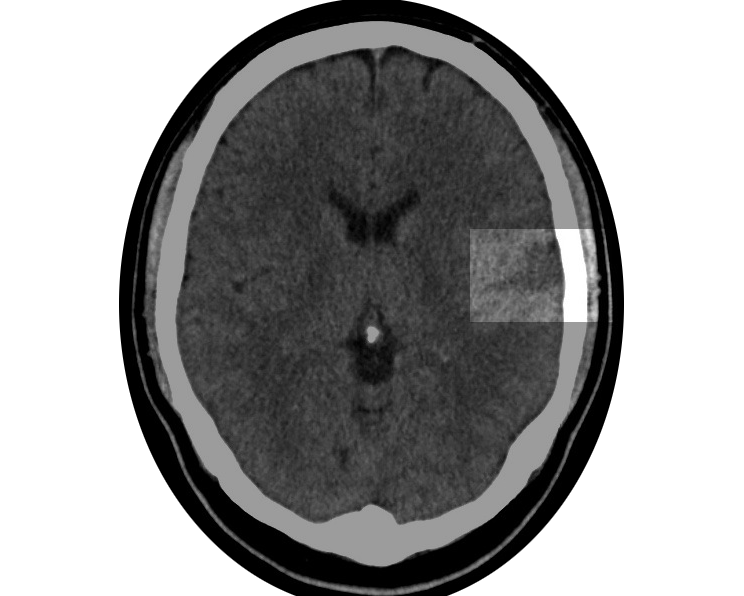

Conclusion: No evidence of acute or subacute intracranial pathology.

Clinical History: Post thrombolysis, 24-hour followup haemorrhage?

Finding Comparison is made with the previous CT brain obtained on 6 May 2017. There is an involving infarct within the left frontoparietal region but no acute intracranial haemorrhage is demonstrated. There is modest associated swelling and mass effect but this is not compromising at present. There is no evidence of inferior frontal or temporal lobe involvement at present.

Opacification is again noted within the right maxillary antrum and ethmoids.

Conclusion Evolving infarct within the left MCA territory involving the frontoparietal region. No features of malignant MCA infarction at present.

Clinical details: Left MCA infarct following weight lifting. No vascular risk factors? carotid dissection.

The left internal carotid artery is occluded from the level of the base of the odontoid peg.

No contrast from this level to the intra petrous level, incomplete opacification of the distal intra petrous carotid bone and intracavernous carotid, presumably retrograde filling via the circle of Willis.

The left cranial arteries outline normally including the MCA branches. The vertebral basilar arteries are normal.

Established infarcts in the anterior and posterior left frontal lobes.

Conclusion. Occlusion of the distal 3 cm of the cervical internal carotid artery, presumably this is due to a dissection. An echo would be useful to exclude a cardiac cause.

(For discloser, I had an echo and it did indeed exclude a cardiac cause, indicating my condition hadn't developed from, or was caused by, a previous health condition. There was also no family history of stroke, so it wasn't hereditary either.)